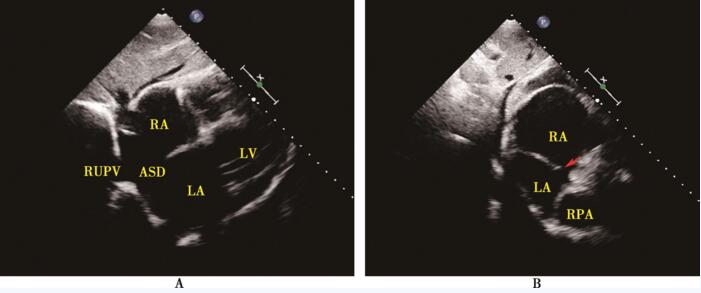

3.临床如何避免漏诊部分型肺静脉异位引流?

右肺静脉与右上腔静脉或右心房连接最常见,约占3/4(图42-3)。其他类型相对少见。一旦房间隔缺损大小与右心房、右心室扩大不成比例时,应仔细扫查肺静脉是否都汇入左心房,通过追踪肺静脉与右心房、上腔静脉、下腔静脉或垂直静脉的关系,基本能够明确肺静脉是否存在异位引流以及具体分型,避免漏诊。

图42-3 超声心动图提示部分型肺静脉异位引流,上腔型房间隔缺损合并右上肺静脉异位引流入右心房

A:剑下四腔心切面显示右上肺静脉异位连接右心房顶部,房间隔近心房后壁可见回声缺失; B:剑下双心房切面显示近上腔静脉房间隔存在回声缺失 (红箭头所示),右心房明显增大。

RUPV:右上肺静脉;RPA:右肺动脉